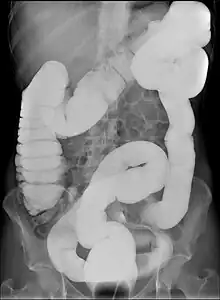

Dolichocôlon

En médecine, un dolichocôlon (mot dérivé du grec ancien dolichos, long et de côlon) est un intestin anormalement long[1]. Il ne faut pas le confondre avec un gros intestin anormalement large, appelé mégacôlon (ou colectasie) .

Le dolichocôlon est souvent une découverte fortuite sur une radiographie abdominale ou lors d'une coloscopie. Ce n'est pas en soi une maladie en tant que telle ne nécessite aucun traitement.